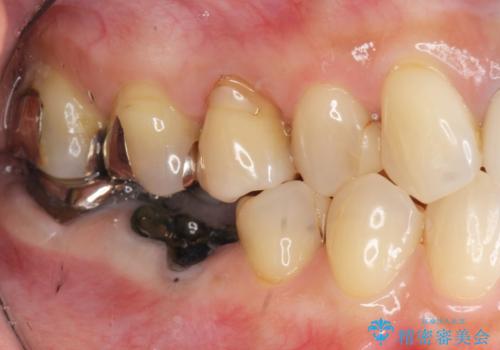

- 銀歯が脱離し、再装着を求めて来院されました。

脱離した歯を精査したところ、大きな虫歯の再発・穿孔箇所が複数認められ長期的な予後を見込むことが難しかったため抜去が妥当であると診断しました。

抜歯後は、奥の銀歯も一緒に白くできるブリッジ治療を希望されました。

(※今回のケースではインプラントも治療の選択肢として可能でした。)